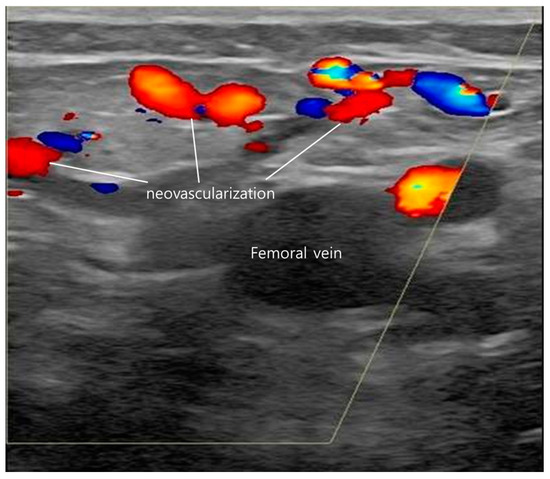

Long-term flush ablation cannot be expected through endovenous thermal ablation alone without complete closure of the cranial tributaries. Even if flush ablation is successful and there is no immediate reflux, if the downward flow of cranial tributaries continues, it can create neovascularization, causing blood flow to proceed downwards, increasing the possibility of recanalization and recurrence of the operated blood vessels. Neovascularization refers to the irregular formation of small collateral vessels in the SFJ area accompanied by reflux (Figure 5). In most cases where neovascularization occurred, the downward flow from the SCIV or SEV was not completely blocked. This is the reason our institution treats the residual tributaries with foam sclerotherapy. Our objective was to completely occlude all inflow to the SFJ region, thereby eliminating any potential for reflux in the GSV.

Regarding the correlation between the recurrence of varicose veins and the neovascularization of SFJ tributaries, of the 47 limbs (4 W EVLA 36 limbs, RFA 11 limbs) recurred, 28 limbs did not have neovascularization, and 19 limbs had neovascularization. Recurrence without neovascularization was additionally treated with revision surgery. The 19 limbs of neovascularization that occurred during the follow-up period were treated with foam sclerotherapy. Foam sclerotherapy is recommended when neovascularization tributaries of the saphenofemoral junction is observed in serial ultrasounds with surveillance [9,11,12,13,14,15].

Figure 5. Neovascularization formed in saphenofemoral junction (SFJ) area. Cranial flow appears red in Doppler ultrasonography.